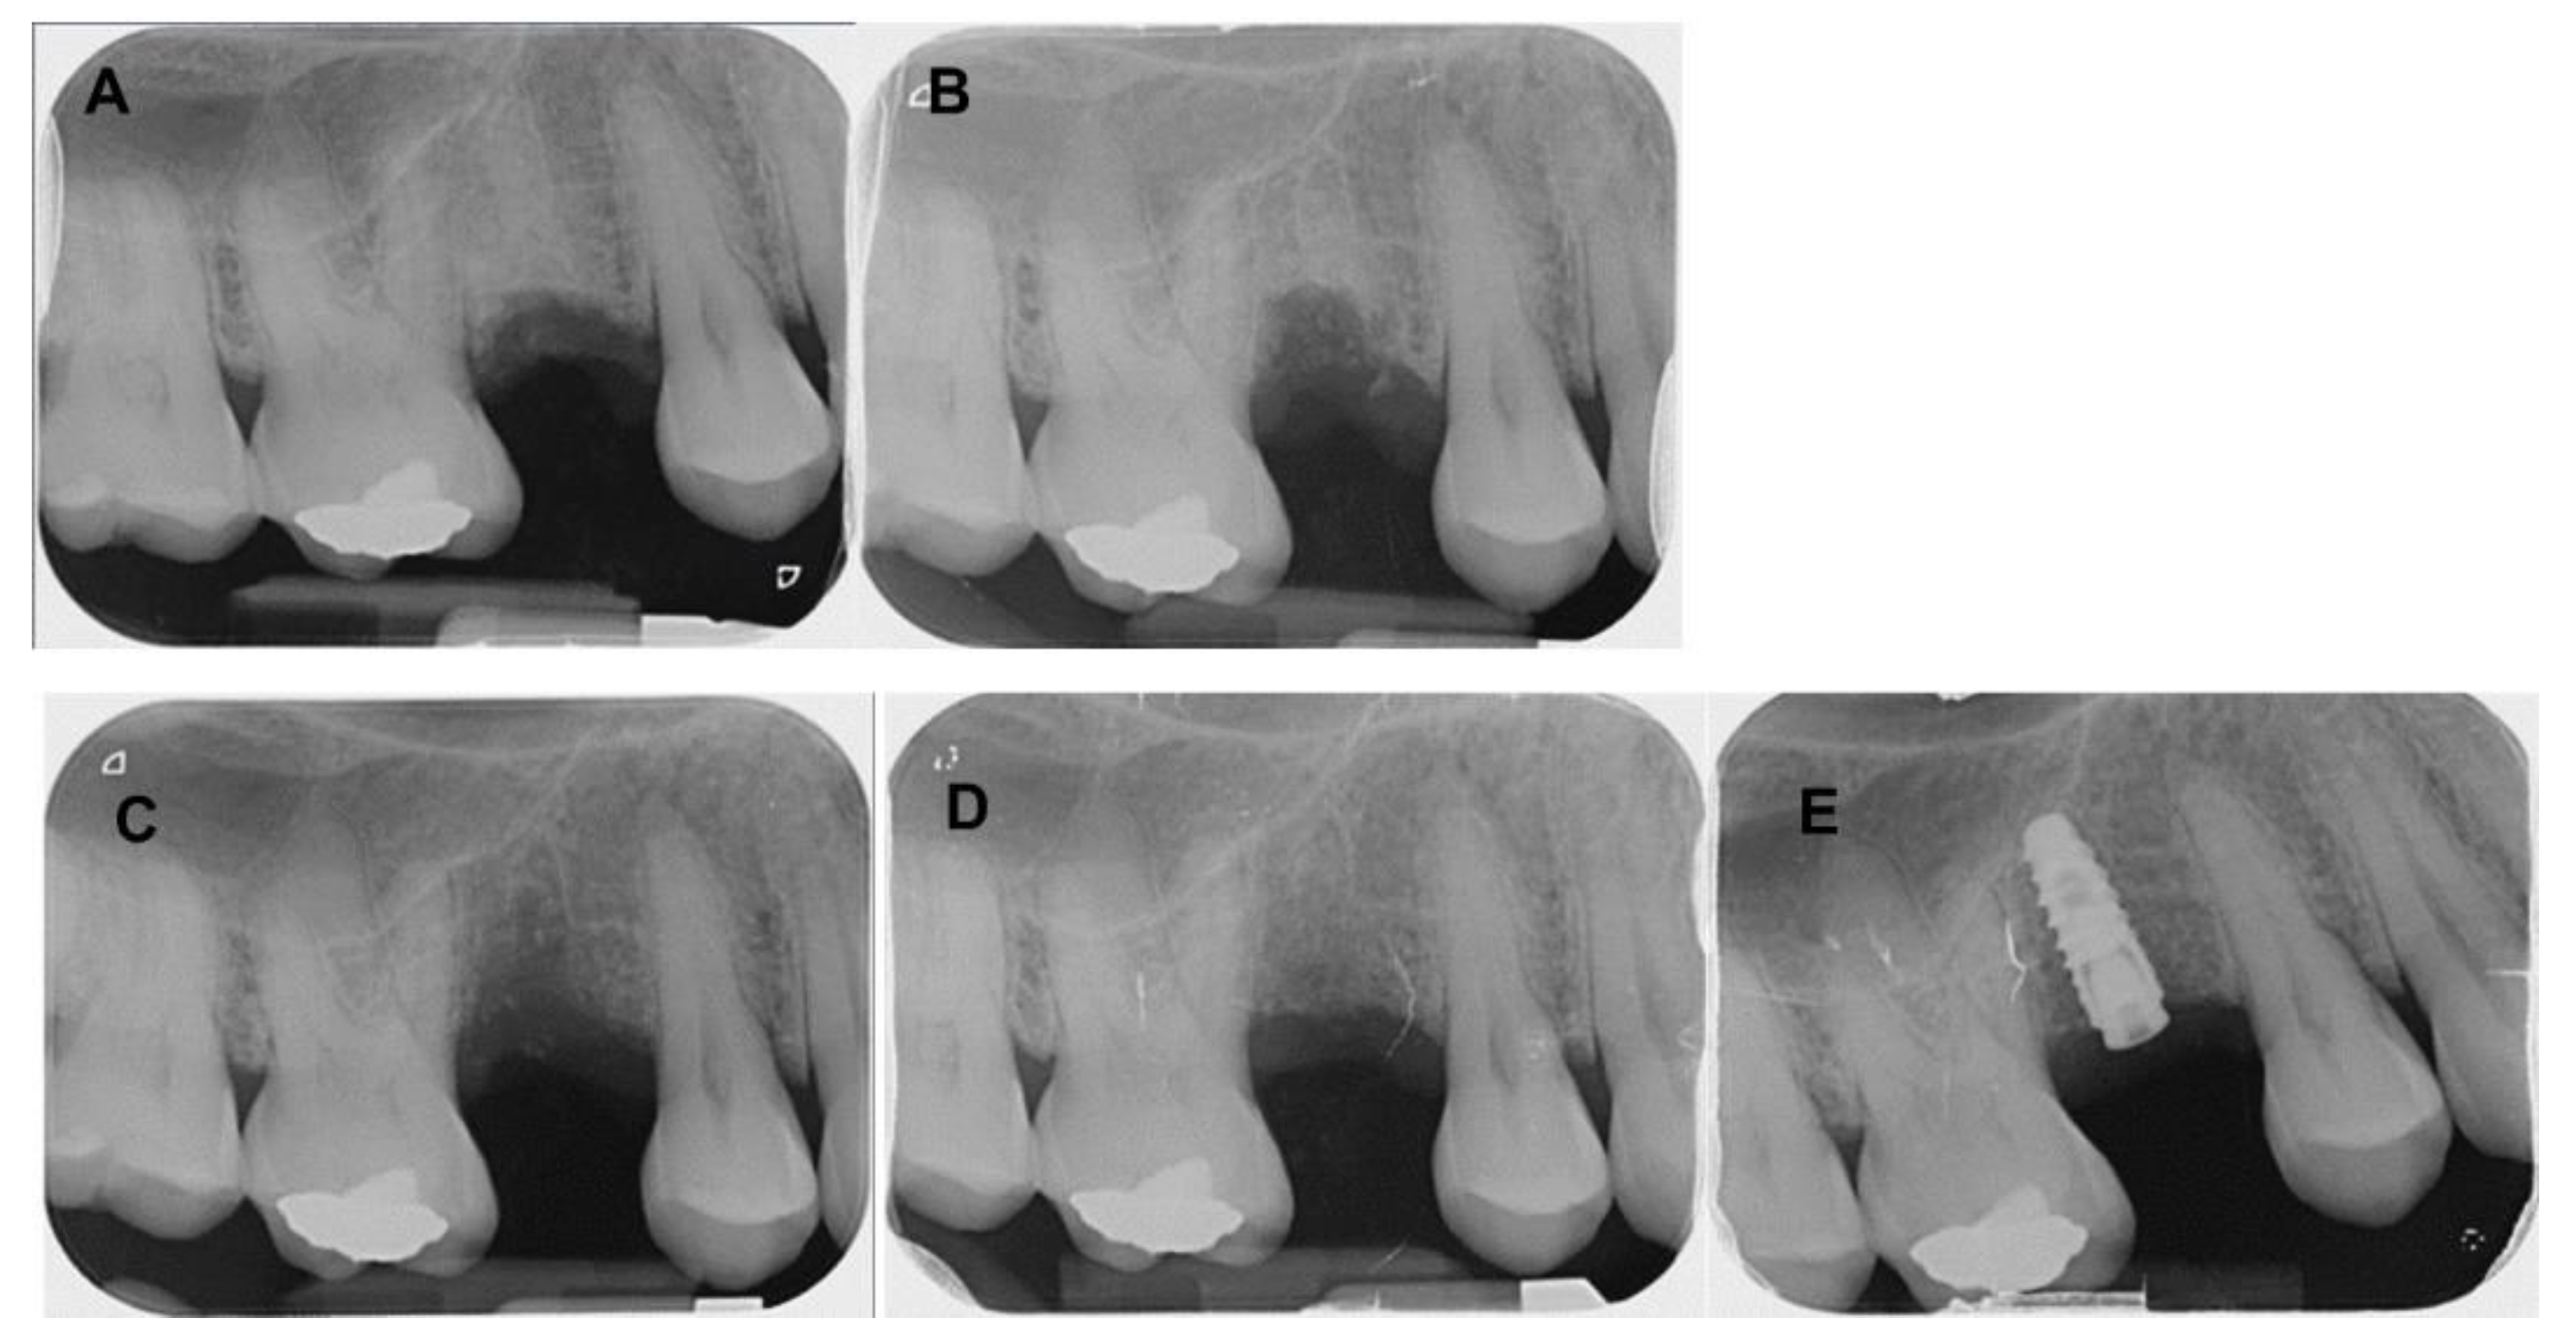

4. Clinical Cases

4.1. Patient No. 1

4.2. Patient No. 2

4.3. Patient No. 3

4.4. Patient No.4

4.5. Patient No.5

4.6. Patient No.6